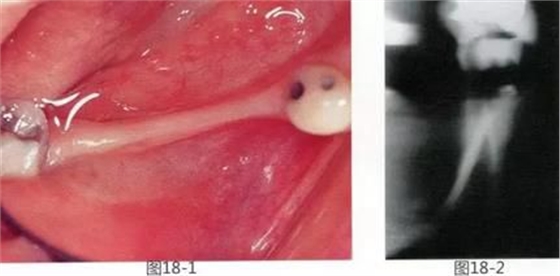

圖18-1 右下磨牙區(qū)牙槽嵴在頰舌側(cè)存在嚴(yán)重的吸收。

圖18-2 同部斷面的X光片。銳利尖角的牙槽嵴形態(tài)。